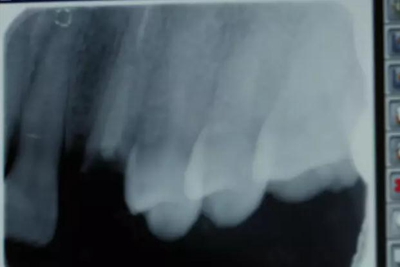

患者男性,35歲,B6銀汞充填后食物嵌塞,要求重新充填,口內(nèi)檢查見B6近中鄰頜面銀汞充填物,局部缺損,有繼發(fā)齲,去除原充填物及繼發(fā)齲,發(fā)現(xiàn)齲壞位于牙齦下方,給予冠延長手術,同期嵌體預備,后一次性取模。(同樣設計為齦上邊緣)

硅橡膠取模后,灌注模型,科爾琥珀樹脂制作嵌體。